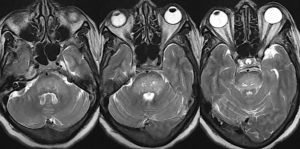

Врач осмотрит вас, чтобы выяснить, какие симптомы вас беспокоят. Важно исключить наличие хронических заболеваний. После этого рекомендуется провести МРТ, КТ, УЗИ головного мозга и позвоночника.

Кроме того, могут потребоваться лабораторные исследования. Они назначаются для исключения воспалительных процессов. После полного обследования врач может определить этиологию боли и рекомендовать соответствующее лечение.